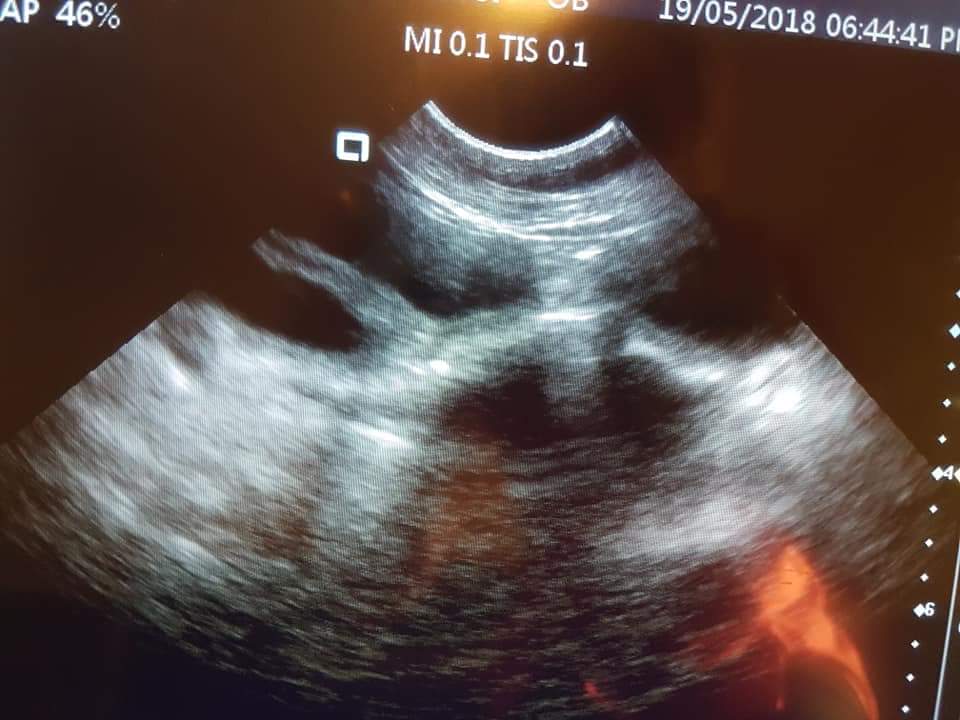

Classic Stump Pyometra YouTube

Classic Stump Pyometra YouTube What Is A Stump Pyometra     — pyometra, characterized by the accumulation of purulent exudate in the uterus, is the most prevalent reproductive. The uterus is generally filled with pus.    — pyometra is an infection of the uterus that may occur in dogs and cats making the pet very ill.  a pyometra (or “pyo”) is a womb infection — a very serious condition. What Is A Stump Pyometra.